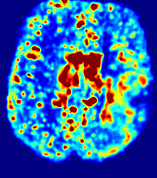

Figure 3: PIANO feature maps for one stroke patient, where the lesion is located in the left hemisphere. Top row: segmented stroke lesion region (white) on different slices, obtained from ISLES 2017. The corresponding slices for the PIANO feature maps are shown in the following rows.

For a better insight into an estimated velocity field 𝐕𝐕{\bf{V}} and diffusion field 𝐃𝐃{\bf{D}}, we compute the following maps: (1) 𝐕rgbsubscript𝐕𝑟𝑔𝑏{\bf{V}}_{rgb}: Color-coded orientation map of 𝐕=(Vx,Vy,Vz)T𝐕superscriptsuperscript𝑉𝑥superscript𝑉𝑦superscript𝑉𝑧𝑇{\bf{V}}=(V^{x},V^{y},V^{z})^{T}, obtained by normalizing 𝐕𝐕{\bf{V}} to unit length and mapping its 3 components to red, green, blue respectively; (2) 𝐕2subscriptnorm𝐕2\|{\bf{V}}\|_{2}: 222 norm of 𝐕𝐕{\bf{V}}; (3) D𝐷D: scalar field in Eq. 5.

Fig. 3 and Fig. 4 show the PIANO feature maps estimated from two ISLES 2017 patients: all are highly consistent with the lesion in both cases. Details of the blood flow trajectories are revealed in 𝐕rgbsubscript𝐕𝑟𝑔𝑏{\bf{V}}_{rgb} by the ridged patterns and the sharp changes of colors in the unaffected (right) hemisphere, while the flat patterns appearing within the lesion provide little directional information about the velocity and indicate low velocity magnitudes. Velocity magnitudes are more directly visualized via 𝐕2subscriptnorm𝐕2\|{\bf{V}}\|_{2}, from which one can easily locate the lesion where 𝐕2subscriptnorm𝐕2\|{\bf{V}}\|_{2} is low. D𝐷D also indicates lower diffusion values in the lesion, though with less contrast potentially due to the fact that it captures the accumulated effect of CA diffusion at the voxel-level.